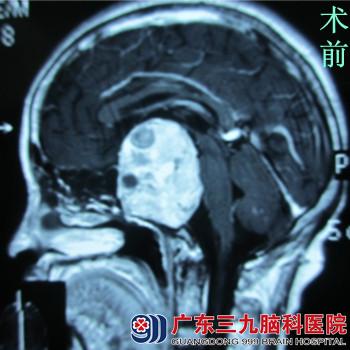

但是近两年来,张阿姨总是感觉看东西模糊,偶尔还有些头晕,刚开始的时候并没放在心上,认为自己是没有休息好。她调整了自己的作息时间,每天按时上床睡觉,有空的时候还和小区里的老姐妹打打太极拳。但是一段时间过去了,不但眼睛模糊没好转,还有加重的迹象。这下张阿姨着急了,随即到附近的一家医院去检查,开了些眼药水便放心的回家了。可是用了一段时间的眼药水后,眼睛并没有好转。近几日张阿姨突然出现了剧烈头痛、食欲差等症状,精神状态极差。家人见后马上把她送到附近大医院就诊,行头颅MRI检查,发现颅内鞍区巨大病变,怀疑垂体瘤。患者家属为求进一步治疗来广东三九脑科医院就诊。

入院后,垂体瘤诊疗中心的鲁明主任在最短的时间内安排了手术。鲁主任指出:因肿瘤太大,无法一次性切完,可通过导航定位技术经鼻蝶入路进行肿瘤切除术,手术经张阿姨的右鼻孔切开鼻中隔后部鼻粘膜,分离鼻粘膜至骨性鼻中隔,止血,沿骨性鼻中隔,分离至蝶窦前壁。显微镜下见肿瘤组织呈淡红色,质地松软,血供一般,刮匙刮除部分病变组织,吸引器吸出残余病变,术中出血少。术后病理报告示:垂体大腺瘤。手术过后,张阿姨感觉自己看东西明显较前清楚了,头痛的症状消失了。2周后张阿姨完全康复出院了,她终于见到了日夜思念的外孙,脸上又露出了幸福的笑容……